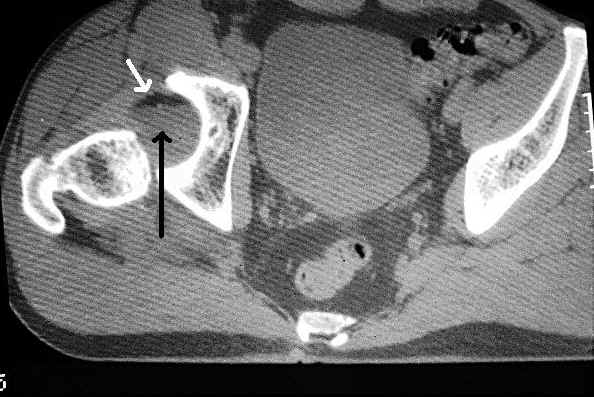

This axial CT demonstrates a posterior dislocation of the right hip with blood and fat filling the acetabular fossa. The white arrow indicates fat layering upon blood (black arrow).